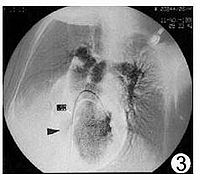

三尖瓣闭锁是一种紫绀型先天性心脏病发病率约占先天性心脏病的1~5%。在紫绀型先天性心脏病中继法乐四联症和大动脉错位后居第三位。主要病理改变是三尖瓣闭锁或三尖瓣口缺失,卵圆孔未闭或房间隔缺损。详细见三尖瓣闭锁。

三尖瓣下移畸形是一种罕见的先天性心脏畸形。1866年Ebstein首先报道一例,故亦称为Ebstein畸形。其发病率在先天性心脏病中占0.5~1%。三尖瓣下移畸形系指三尖瓣畸形,其后瓣及隔瓣位置低于正常,不在房室环水平而下移至右心室壁近心尖处,其前瓣位置正常,致使右心房较正常大,而右心室较正常小,可有三尖瓣关闭不全。此类畸形常合并卵圆孔开放或房间隔缺损以及肺动脉狭窄。由于右心房内血量较多,压力增高,其所含血液部分经房间隔缺损或卵圆孔流入左心房,部分仍经三尖瓣入右心室,因肺动脉狭窄,进入肺循环的血量减少,故回入左心房的动脉血量也少,此时再与自右心房分流来的静脉血混合,经二尖瓣而入左心室体循环。详细见三尖瓣下移畸形。